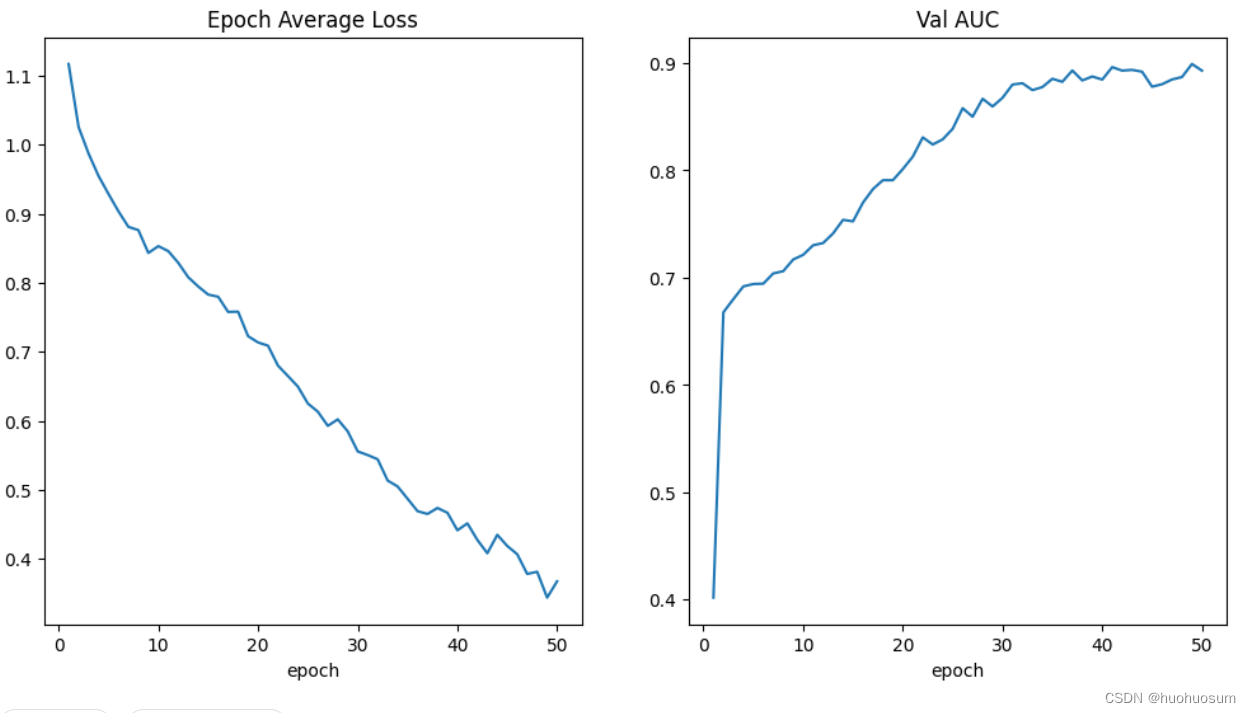

训练过程中损失函数与AUC变化曲线如图所示:

可以看出,随着训练次数的增加,损失不断减小,AUC不断增加。

本文先总结归纳了MONAI框架进行医学图像分类的基本步骤,然后经过对BUSI数据集进行分析,提出了例程代码修改思路,并逐步展示了如何修改MONAI例程代码以适应新的数据集应用,为初学者上手MONAI提供了参考。现在模型的估计效果还不是最优,我认为有两个原因,一个是数据量比较少,只有700多张图像,而MedNIST有万张图像,可以支撑模型实现0.99的预测准确率;二是超声图像数据在缩放过程丢失了一些信息,可能会降低模型的识别能力。如果要提高模型预测性能,可以从两方面着手:一是进行数据增广,提高数据多样性;二是增加训练次数,从训练曲线上看,损失函数和AUC都有持续优化的趋势。